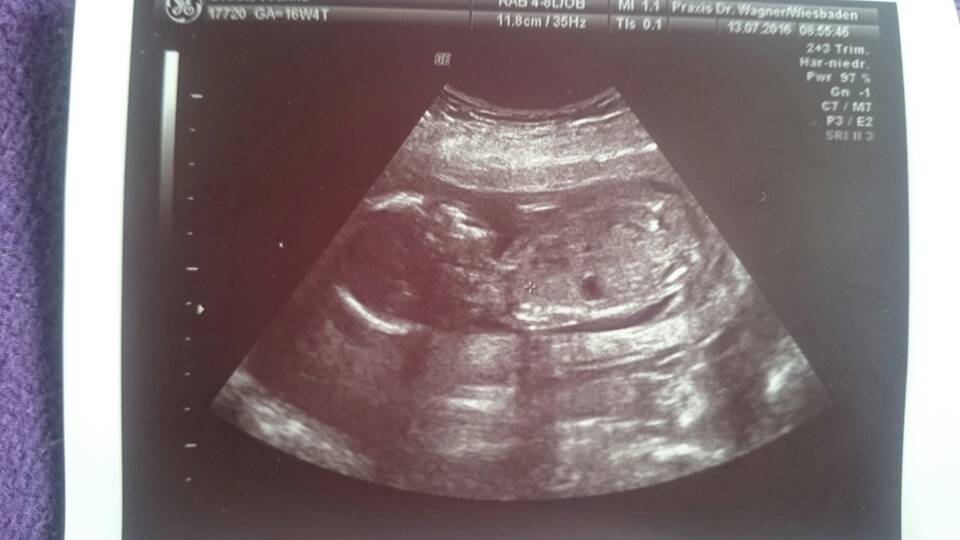

Tak więc dzidziuś ma się bardzo dobrze, ma piękne bijące serduszko, waży 150g, ma silne rączki i nóżki które odpychaly się od głowicy usg.przez co nie za bardzo dał się podglądać. Lekarz usilnie próbował zobaczyć czy Fabian został Fabianem, no ale było tak ułożone poprzecznie że ani dopochwowo ani przez brzuch nie pokazało się nam w pełnej okazałości. Lekarz mówił że z tym synem to mógłby sie trochę poklocic, bo to co dziś udało mu sie podglądać wcale aż takie chłopięce nie było. I szansę na Lene wzrosły. Cierpliwie tłumaczył, ze za 4 tyg będę miała usg polowkowe i takie badanie bedzie trwało ok 30-40 minut więc mamy szansę żeby dzidziuś pobracal sie trochę co da nam więcej możliwości zagladnac między nogi.

Szyjka bardzo długa, łożysko wysoko zdala od ujścia szyjki. Plamienia mogą się jeszcze pojawiać do 20 tyg i mam być spokojna, bo o ile nie ma krwi to jest bardzo dobrze.